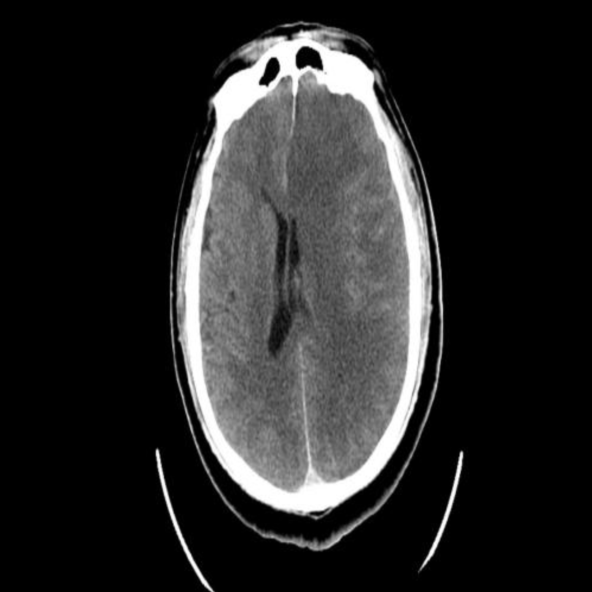

急诊头部CT:左侧脑组织密度减低,水肿,脑沟、脑回变浅、脑室受压,左侧大脑中动脉高密度征。

入院CT